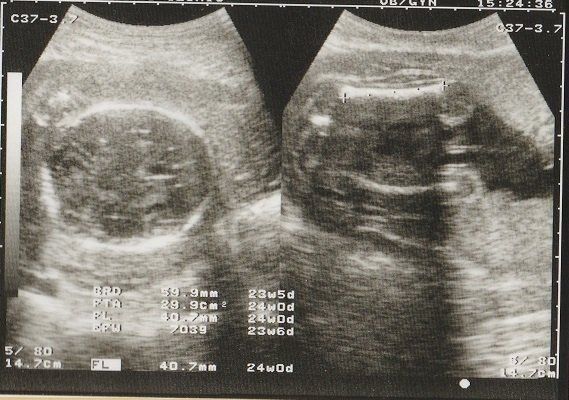

妊娠24週目のエコー写真 早産のリスクがある時期

日常生活が大変な時期になってきました。早産の心配もあるので、重い荷物は持たないようにするなど気をつけました。

右側は赤ちゃんの顔の画像。目鼻も何となくわかって、「ああ顔だなあ」と思えるようになりました。